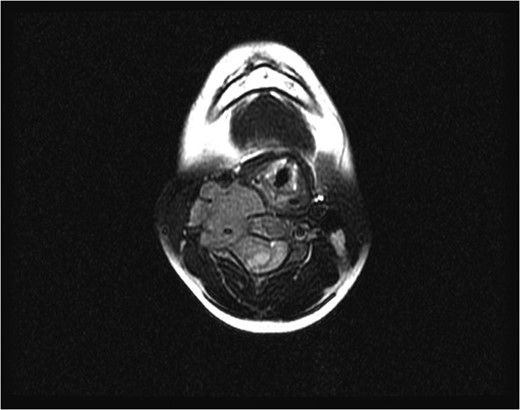

Axial magnetic resonance image after the first surgery, showing complete resection of the intraspinal component of the tumor, with a residual tumor and presence of a spinal cord signal at the C4 level.